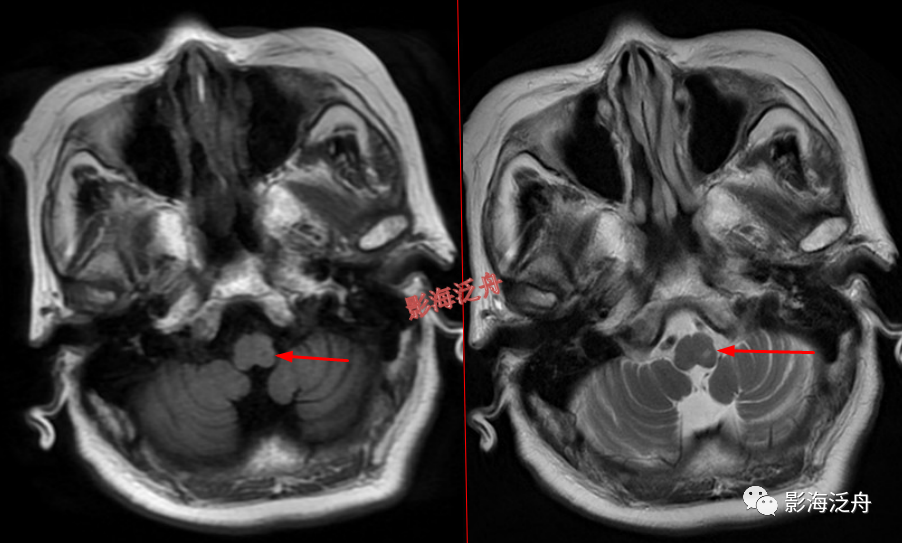

颞极前方蛛网膜囊肿(红箭)漏诊率也比较高,尤其在老年患者中,常常被误认为是扩大的蛛网膜下间隙,仔细观察可以发现右侧颞叶受压,脑沟闭塞(绿箭),与健侧(蓝箭)对比更为明显。

右侧侧脑室体部囊性占位(红箭),整体信号与脑脊液一致,病灶边缘部分显示,透明隔稍移位。